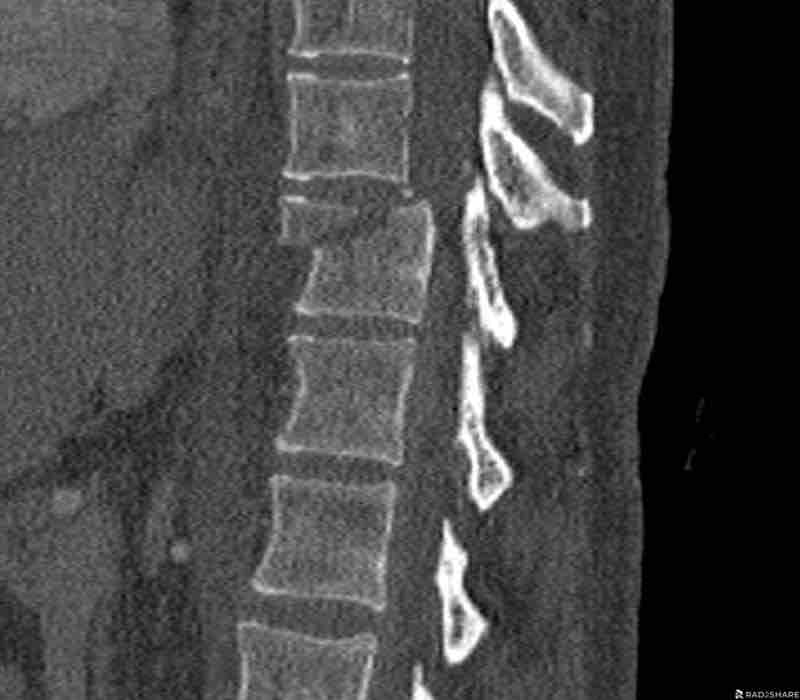

What is the highest AO-type of injury?

Findings

- No C or B injury.

- Fractures of the vertebral body with involvement of both endplates (1+1 points) and posterior wall (2 points).

- In the coronal plane, a sagittal course of the fracture is seen, which is common in burst fractures.

- Bulging of the posterior wall without any other signs of dislocation is the result of the burst fracture.

Therefore no C injury.

Conclusion

Injury type A4